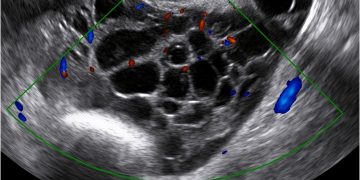

Cari soci, finalmente online le soluzioni dei casi di Maggio!!! Caso 1 Scarica il File Caso 2 [pdf-embedder url="https://www.sieog.it/wp-content/uploads/2022/05/caso-clinico-maggio-2-risposta.pdf" title="caso...